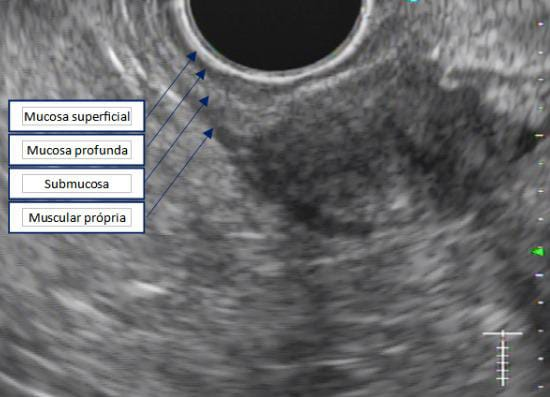

Com relação à ecoendoscopia, o método permite avaliar com muita precisão as camadas e interfaces do trato gastrointestinal, sendo o melhor método de imagem para avaliar e caracterizar as lesões subepiteliais. Com uma frequência de varredura entre 5 a 12 MHz, o ultrassom endoscópico permite distinguir as paredes do TGI em 5 camadas: mucosa superficial (1ª camada ou interface fluído luminal e mucosa), mucosa profunda (2ª camada ou muscular da mucosa), submucosa (3ª camada), muscular própria (4ª camada) e serosa (5ª camada) (figura 4)15,24-26.

Imagem 1. Sinal da almofada (“pillow sign”) Fonte: Kim GH et al.16Imagem 2. Sinal do rolamento (“rolling sign”) Fonte: Kim GH et al.16Imagem 3. Sinal da tenda (“tenting sign”) Fonte: Kim GH et al.16Imagem 4. Ecoendoscopia demonstrando lesão com ecogenicidade hipoecoica, ecotextura homogênea, arredondada, limites bem definidos, contornos regulares, medindo 15 mm x 12 mm e inserida na camada muscular própria. A imagem permite demonstrar as camadas mucosa superficial, mucosa profunda, submucosa, muscular própria. Fonte: arquivos do Instituto do Câncer do Estado de São Paulo (ICESP/HCFMUSP).